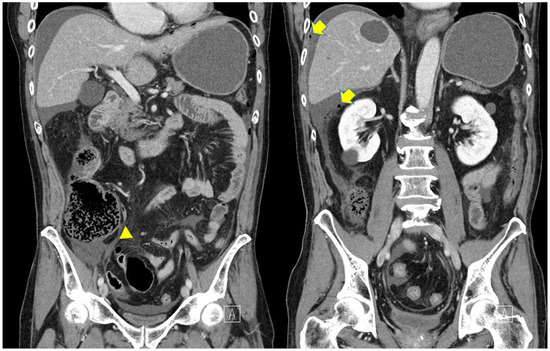

A computed tomography (CT) image revealed a dilated cecum surrounded by free air, while the appendix was intact (Figure 1). The preoperative diagnosis was perforation of the cecum. We planned to perform an urgent laparoscopic surgery.

Figure 1.

Computed tomography (CT) images revealed dilated cecum and free air. Arrowheads indicate appendix and Arrows indicate free air, respectively.